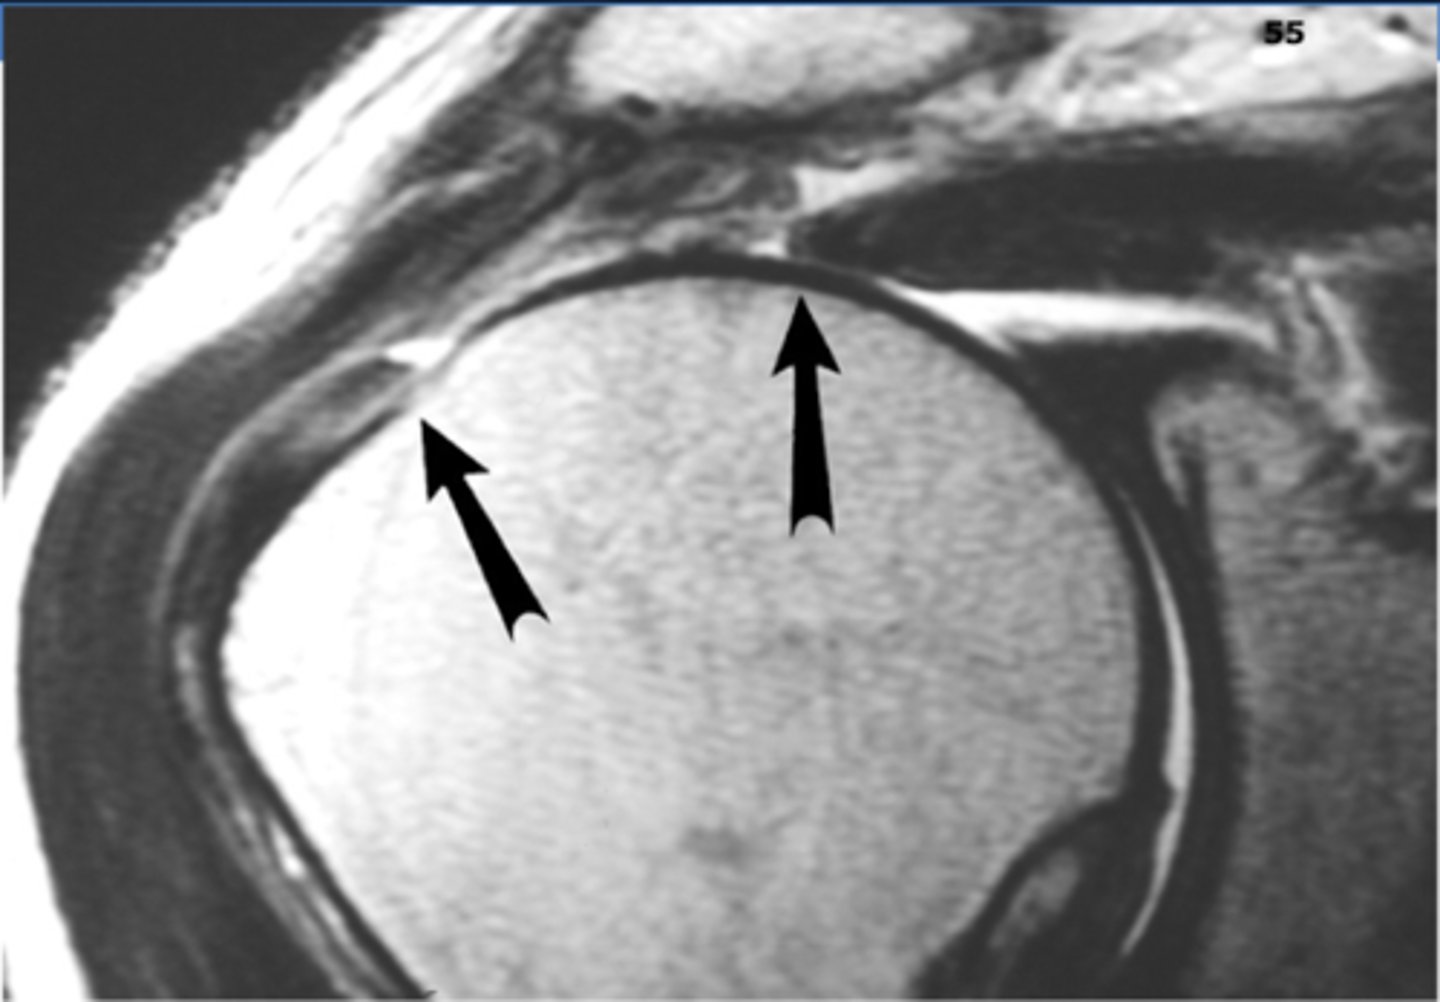

What diagnostic imaging study can CONFIRM the presence of a RTC tear?

MRI

What is a Hill-Sachs lesion?

compression fracture of posterior humeral head due to ANTERIOR dislocation

What is a Bankart lesion?

glenoid labrum tear in the anterior joint that occurs due to an ANTERIOR dislocation most commonly